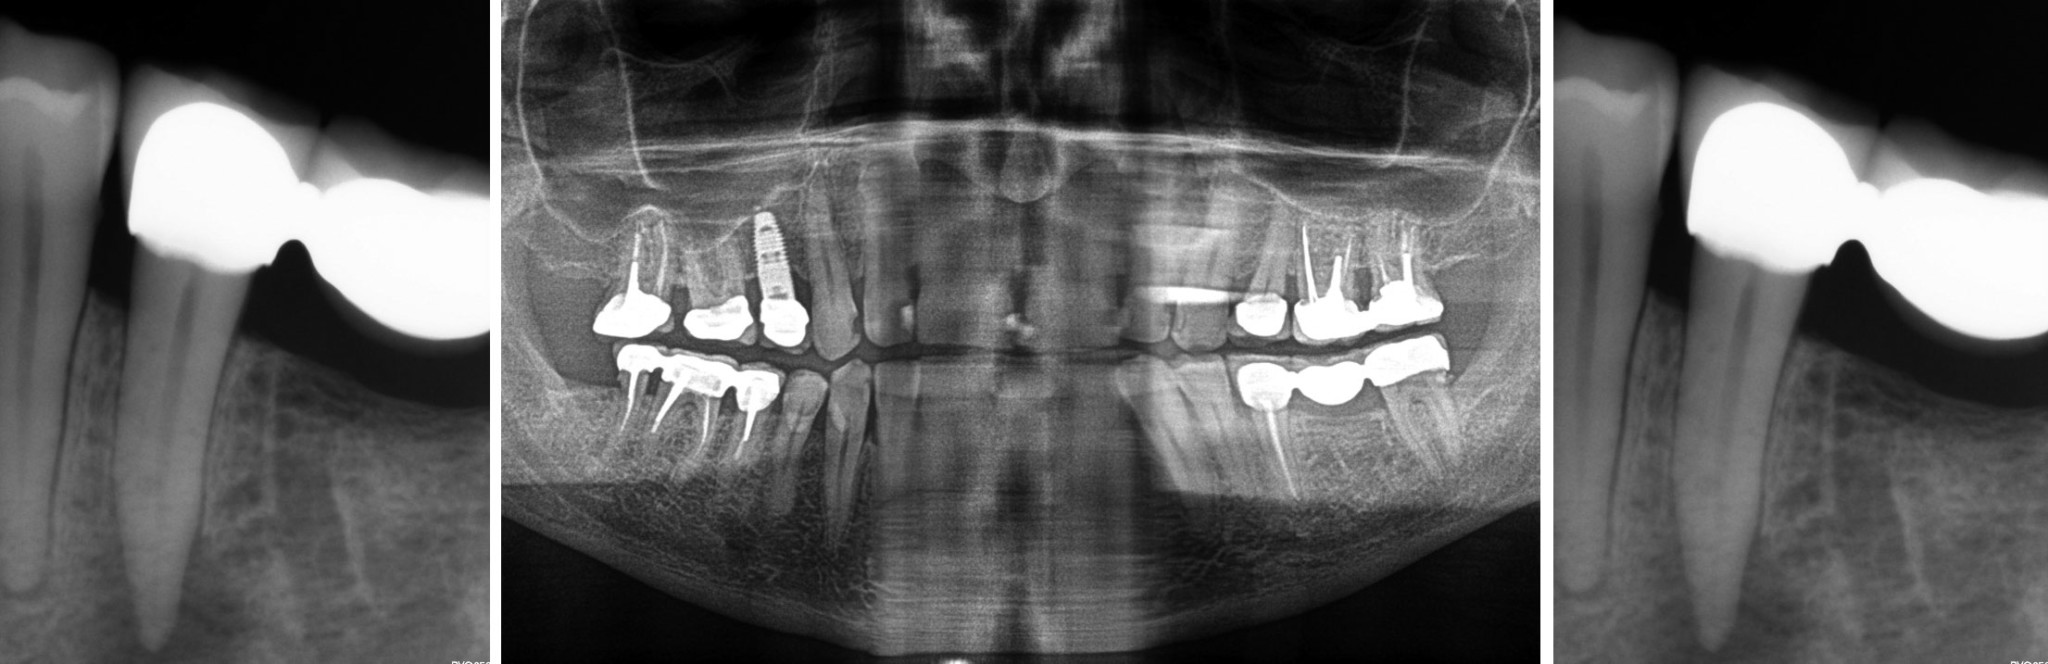

Gran lesión apical en piezas 4546. La importancia de un correcto diagnóstico endogalicia

On l'appelle kyste apical, granulome, lésion d'origine endodontique ou encore lésion apicale Le traitement peut inclure une intervention endodontique ou une extraction. Est-ce que cette description oriente toujours vers un lien entre lésion apicale sous couronne (s), peut-être même fissure - et névralgie type migraine ? Les radios simples des 24-25 semblent normales; les lésions apicales ressortent au scanora seulement.

Kystes et granulomes péri apicaux traitement laser Dentiste Docteur Gérard Rey. La résection apicale,c'est quoi ? J'ai mal mal sous une couronne,soit à la mastication soit au froid et au chaud Dévitaliser une dent c'est quoi exactement? Le granulome dentaire est une lésion inflammatoire à la racine d'une dent, causée par une infection bactérienne